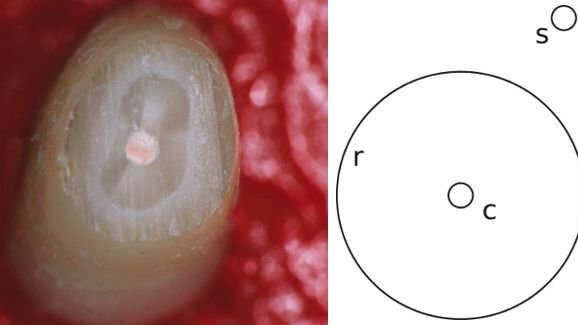

V kliničnih testih je sodelovalo osem endodontskih strokovnjakov iz Nove Zelandije v letih 2002 in 2006 in raziskovalci so ugotovili, da so zobozdravniki podvrženi Delboeufovi iluziji, zaradi česar so zaprta področja videti manjša, kot so v resnici, gledano v širšem prostoru. V njihovem primeru se zdi, da je kaviteta manjša, ko je okoljno tkivo v območju parametrov iluzije, kar vodi v odstranitev preveč zdravega tkiva na škodo bolnika.

Raziskovalci so v poročilu navedlii, da ostaja neznano, ali se zobozdravniki zavedajo tega pojava pri vrtanju in priporočajo, da se njihove ugotovitve vključi v zgodnje faze kliničnega usposabljanja, da se zmanjša tveganje za zlome ali perforacije apikalnega segmenta korenine, ker se odstrani preveč zdravega tkiva. Prav tako predlagajo razširitev posledic pojava vizualne iluzije na druga področja zdravstva.

V zadnji študiji je bilo vključenih več kot 20 primerov ekstrahiranih polnjenih korenin vsakega posameznega zobozdravnika, ki niso bili obveščeni o parametrih iluzije. Udeležencem raziskave so naročili, da morajo odstraniti čim manj tkiva, kot je to mogoče pri obravnavi zoba in pri uporabi svojih običajnih ročnih instrumentov.